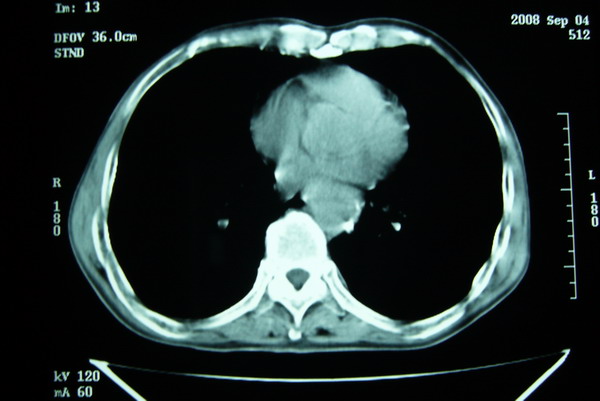

标题: CT15579:男 86岁 咳嗽 咳少量白痰 发热2天 吸烟史60年 [打印本页]

标题: CT15579:男 86岁 咳嗽 咳少量白痰 发热2天 吸烟史60年

右肺上叶巨大软组织肿块,轮廓不规则,纵隔内有肿大淋巴结,首先考虑肺癌。

右上肺一不规则团块,边缘有分叶和毛刺,纵隔有淋巴结肿大。右肺周围性肺癌首先考虑。